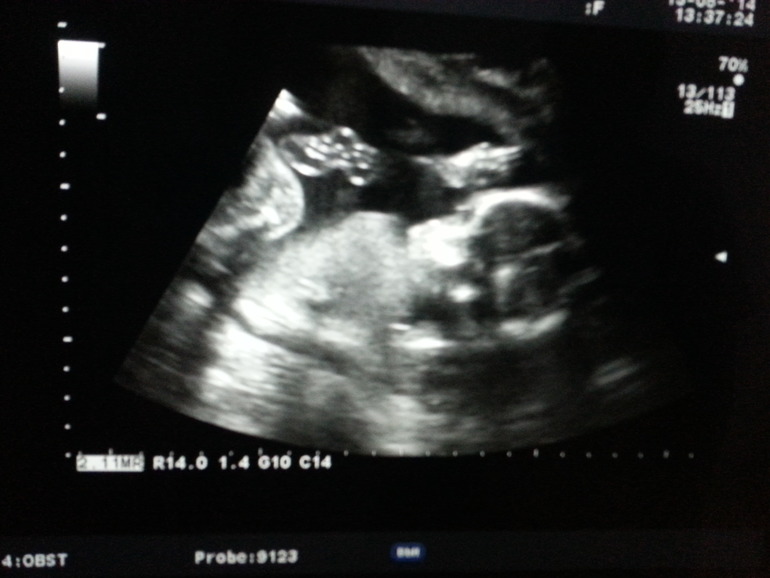

О хорошемПришла нам 20 неделька .сходили мы на узи.посмотрела я своего пусик а. Вес им мы уже целых 407 грамм.показали мне и ножки и ручки и пальчики и носик и глазки

.в жк узисты очень хорошие обажаю их.долго мне его показывали. Здоровенный мой сыночек. Мое солнышко.разрешили сфоткать .долго не Могли уловить его.он такой большой что в экран не влазит. а сейчас лежу думаю дай детскую мелодию включу. И к животу поднесла.он сразу давай там вертеться крутиться. И Пинается. Думаю не понравилось ему что ли?

Как это не увидел? Я сразу увидела, хотела еще прокомментировать, что ручкой машет:))) Поздравляю с УЗИ. Здоровья вам!

Да я ему тоже говорю.тут же видно не вооруженным взглядом. Что он ручкой машет. Ну не видит и все тут.а я думала он посмеется на фоткой))) спасибо огромное